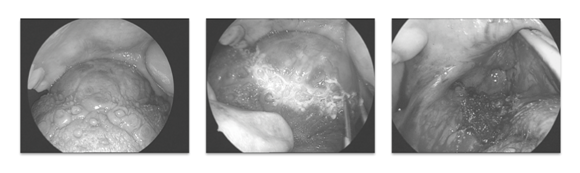

An eighteen year-old girl presented with 5months history of hot potato voice, dyspnoea and dysphagia. On examination, there was a base of tongue mass occupying the oral cavity, obstructing the airway. MRI showed a well-defined BOT mass displacing the epiglottis posteriorly, occupying the entire oropharynx and valleculae, with feeding vessels from both lingual arteries (Figure 1).

Figure 1 MRI imaging for Case 1.